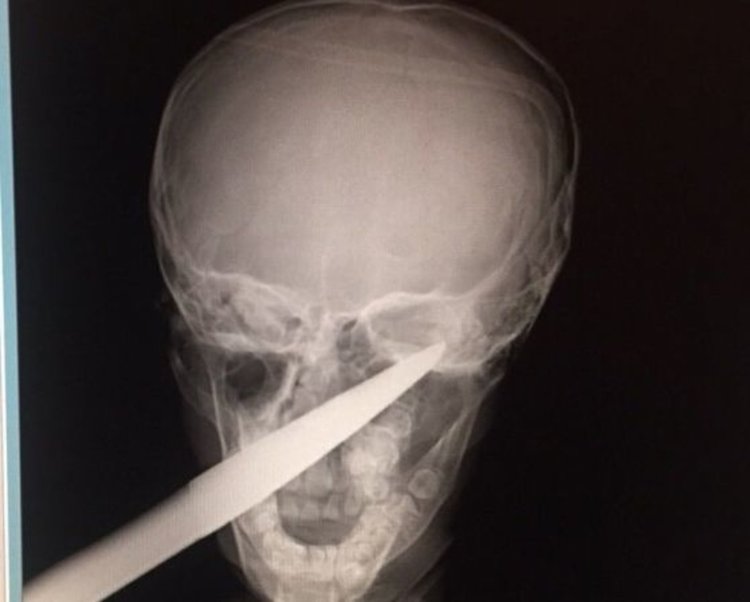

7-годишно момче със забита в главата градинска ножица беше спасено в УМБАЛ-Бургас.

Родителите обясняват, че детето е паднало върху ножицата, докато си е играело в градината. Ръждясалото острие минало през цялата буза и опряло в черепа зад окото, съобщиха от болницата.

Градинската ножица е с размер около 70 см.

"Още няколко милиметра и изходът щеше да е фатален", коментират дежурните лекари.

"В цялата си над 30-годишна практика не съм виждал подобна травма. Оприличавам я на нараняване от военно време, каквито наранявания в днешни дни са рядкост. Острието на ножицата прилича на копие, на щик", посочва УНИГ-специалистът д-р Даниел Петков, който е извършил операцията.

По време на интервенцията ножицата е извадена много бавно, а кървенето е овладяно. Наложило се е кръвопреливане.